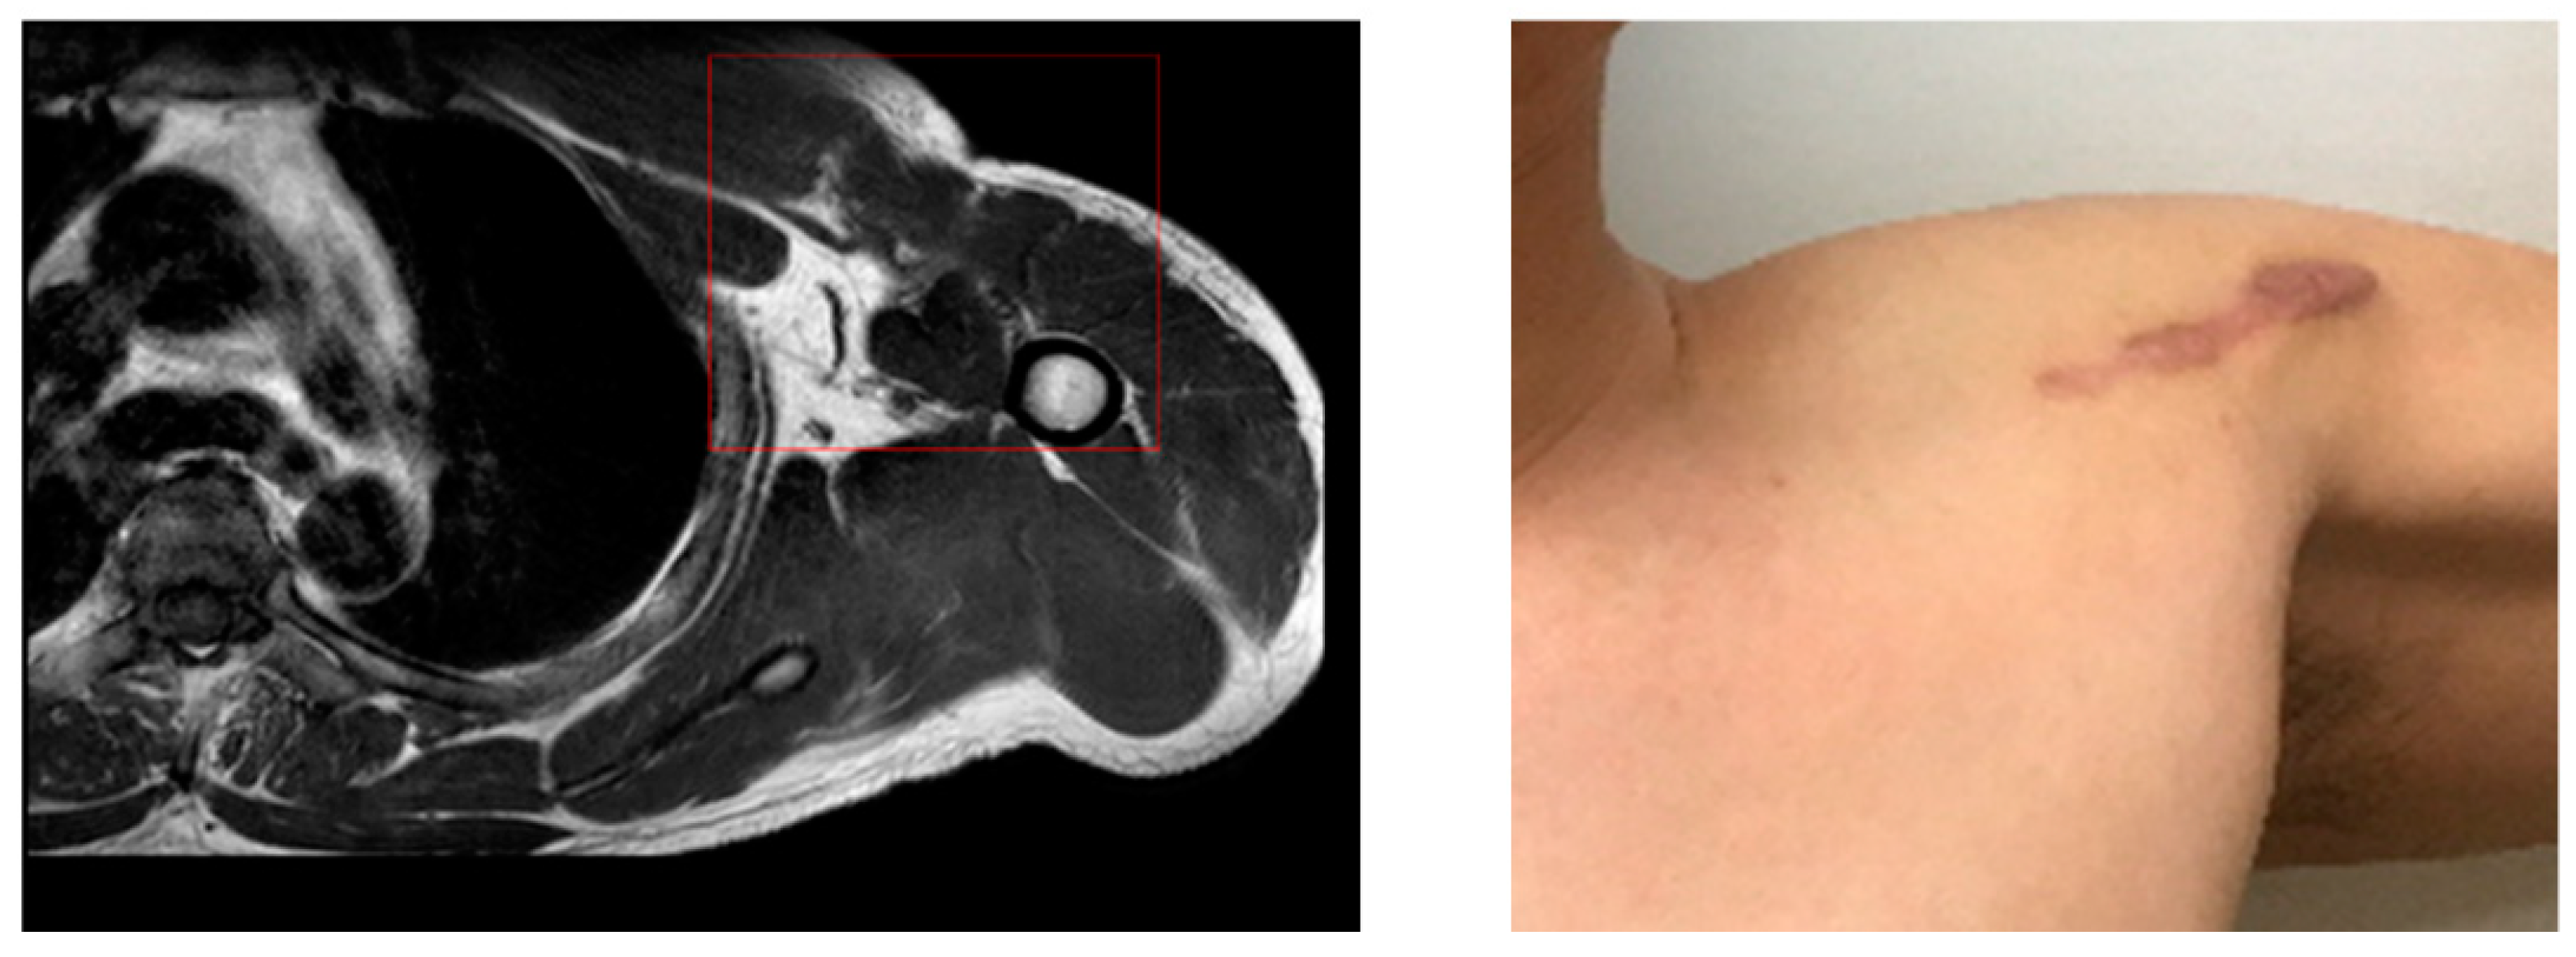

2.3. Therapeutic Intervention: Surgical Treatment

The operation was performed with the patient in the beach chair position, and the approach was done in the deltoid–PM junction. First, the surgery was performed by releasing the surrounding scar tissue and connecting the ruptured area using a knot on the anchor. After the last knot, the shoulder motion and the repaired section were checked, and the skin was sutured after confirmation that there was no abnormality. The patient was discharged after 5 days with a sling (Figure 2). The patient was referred to a sports medicine center after discharge, supervised rehabilitation was conducted for 6 months, and an examination was conducted after one year.

Figure 2. Surgical process.